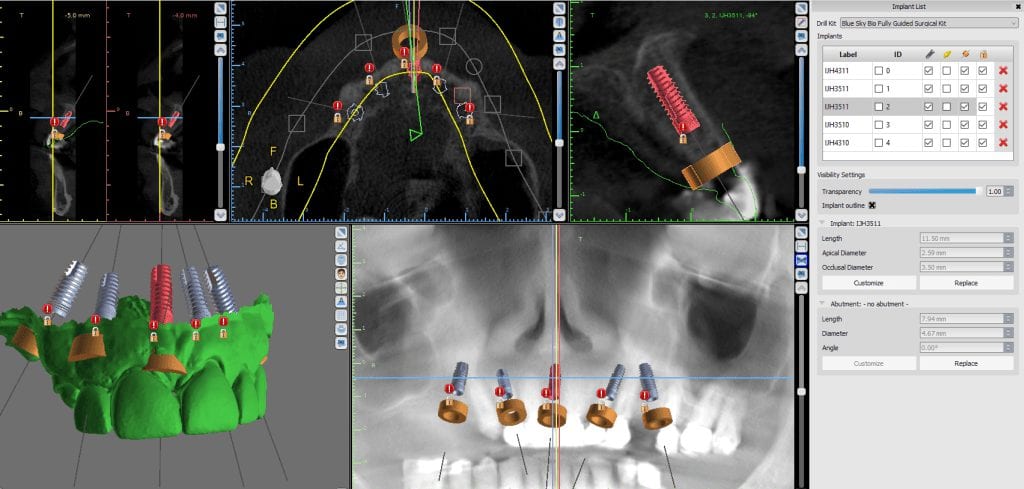

April 5, 2020If you’re experienced with CAD/CAM technologies in dentistry, you probably already know how important file types and system integrations can be for the outcome of a project. In this video, […]